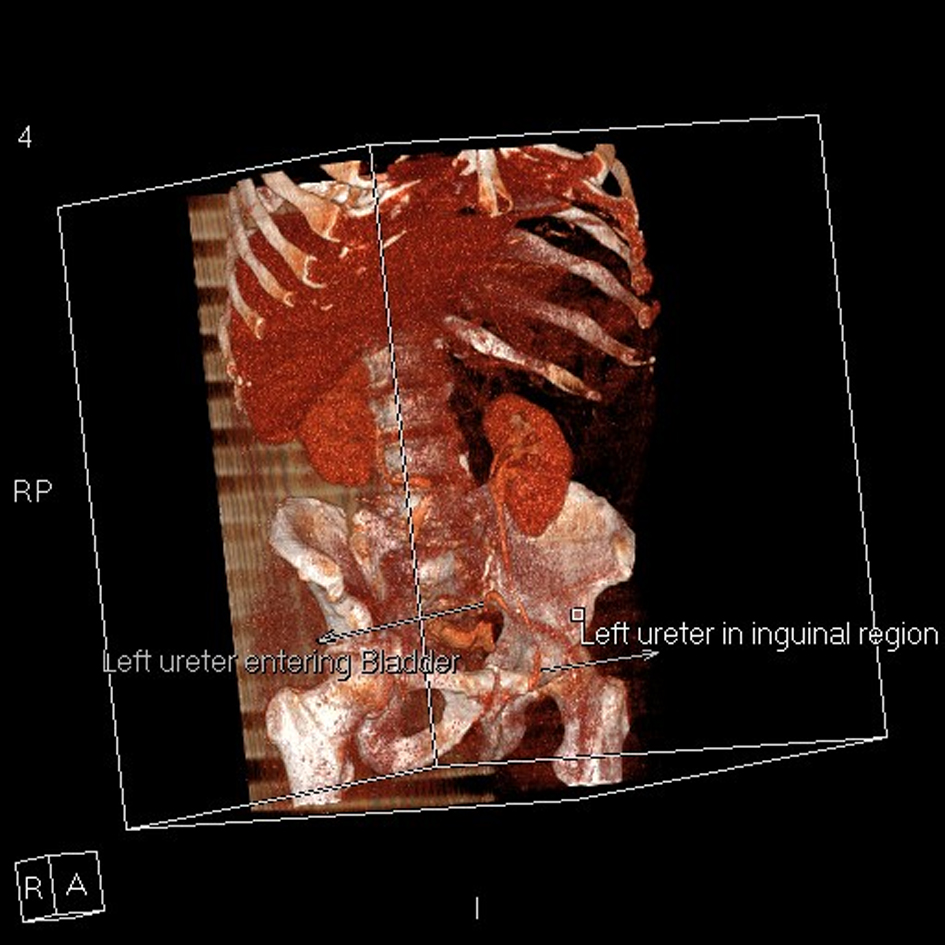

An 83-year old male with benign prostatic enlargement (BPE) presented with acute urinary retention with renal failure, constipation and weight loss. On examination, he had large bilateral asymptomatic inguinal herniae. Following catheterisation and medical renal failure management, a contrast-enhanced CT scan was performed to investigate his constitutional symptoms. An incidental finding was partial left ureteral duplication, and urography revealed that the distal part of one limb looped into the left inguinal hernia before inserting into the bladder (Fig. 1-4). The patient’s renal function normalised with catheterisation, which was definitive management of his BPE due to medical co-morbidities.

![]() Click for large image | Figure 4. 3-D reconstruction of abdominal and pelvic CT urogram demonstrating one limb of the partially-duplicated left ureter entering and leaving the inguinal canal before entering the bladder. |